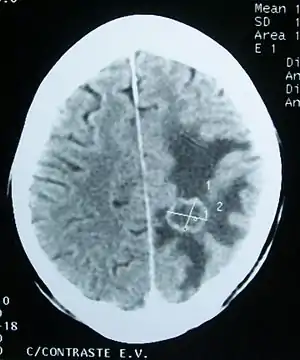

![]() Набряк речовини головного мозку (темна ділянка) навколо метастатичної пухлини (комп'ютерна томограма) Набряк речовини головного мозку (темна ділянка) навколо метастатичної пухлини (комп'ютерна томограма) | |